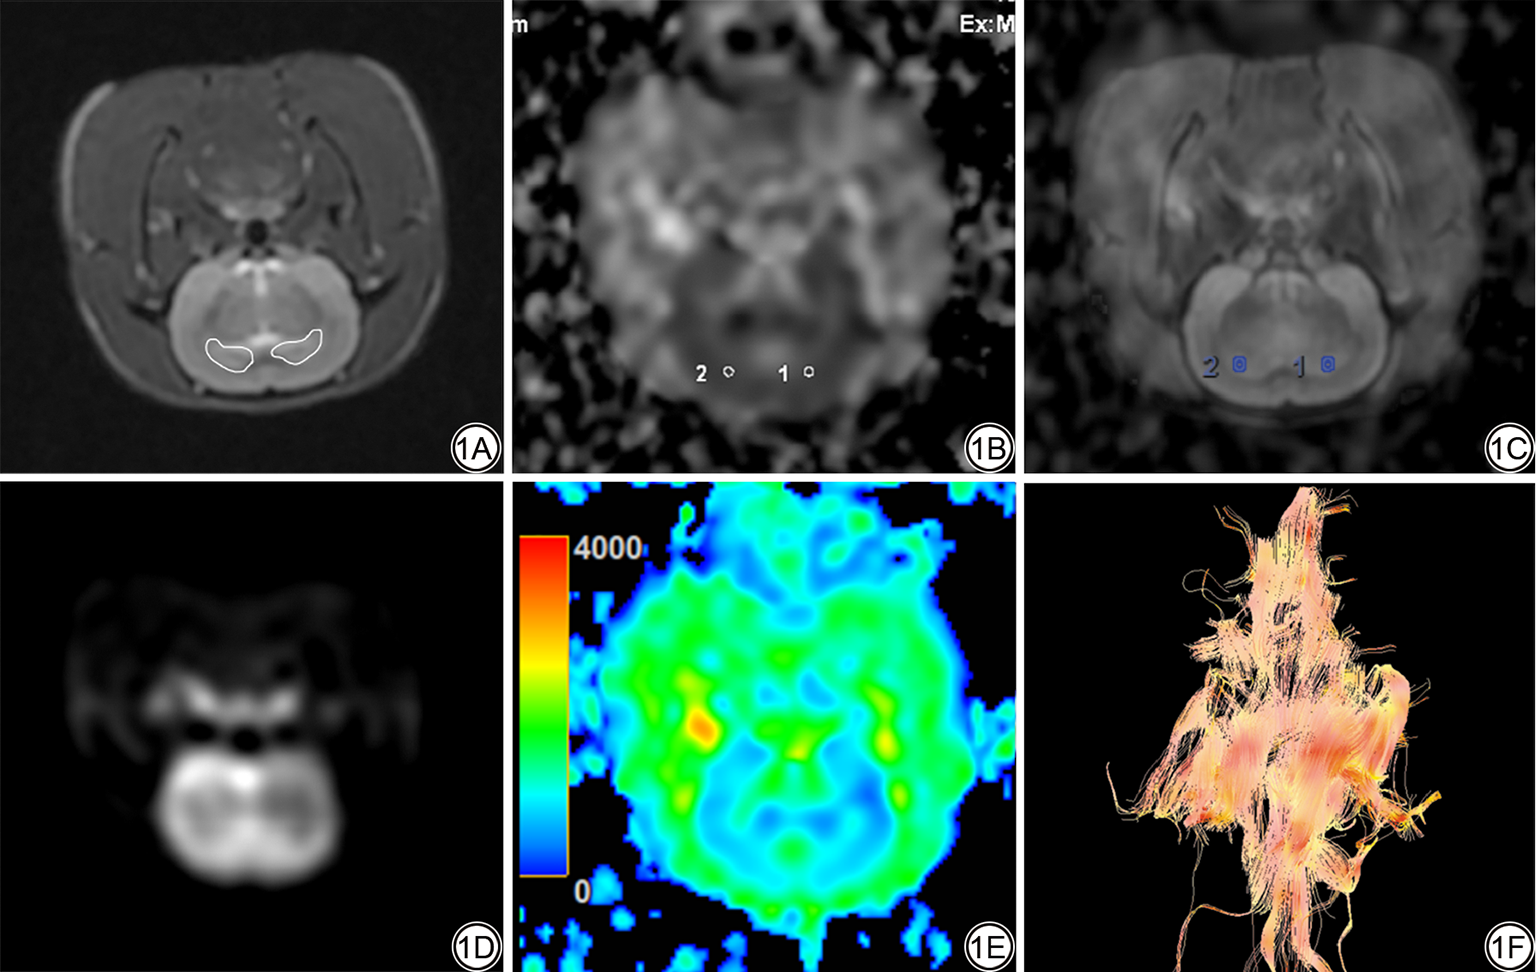

DTI图像及ADC值均通过设备自带的ReadView(GE Healthcare,美国)软件获取。定位将海马体选择为感兴趣区(region of interest, ROI)。ROI的选择由1名放射科主治医师(具有7年诊断工作经验)进行勾画,该医师对实验过程及动物分组情况不知情,同时由放射科副主任医师(具有10年以上诊断工作经验)审查图像,确定ROI勾画区域的一致性。测量时通过T2WI与ADC序列融合图像为主要定位依据,辅助参考T2-FLAIR序列区分海马体与周围脑区,清晰显示海马体“C”形结构的完整轮廓,确保选择的ROI位于明确的海马体解剖边界内,避免包含海马体周围的脑脊液、血管或水肿区域,以海马体最大截面层面为勾画层面,ROI为类圆形,勾画双侧海马体主体区域,双侧ROI基本对称,面积2~3 m2,分别获取两侧海马体测量值,并对两次测量值取平均值。见图1

图1  SAH后大鼠海马区MRI图像。1A:大鼠原始T2-FLAIR序列图,白色圈为双侧海马体最大截面;1B:大鼠原始ADC序列图,于海马体对称位置勾画ROI(白圈);1C:T2-FLAIR与ADC序列图融合图像,蓝圈为勾画双侧海马体ROI;1D:大鼠原始DWI序列图;1E:大鼠原始ADC伪彩图;1F:大鼠脑DTI纤维束图。SAH:蛛网膜下腔出血。T2-FLAIR:T2加权液体衰减反转恢复序列;ADC:表观扩散系数;ROI:感兴趣区;DWI:扩散加权成像;DTI:扩散张量成像。

Fig. 1  MRI images of the rat hippocampus following SAH. 1A: The raw T2-FLAIR sequence images of rats, with white circles represent the maximum cross-sections of the bilateral hippocampi; 1B: The raw ADC sequence images of rats, with ROIs delineated at the symmetric positions of the hippocampi (white circles); 1C: For the fused image of the T2-FLAIR and ADC sequence images, with blue circles delineating the ROI of the bilateral hippocampi; 1D: The raw DWI sequence image of the rat; 1E: Pseudocolor map of the rawl ADC in rats; 1F: Fiber tractography map of rat brain DTI. SAH: subarachnoid haemorrhage; T2-FLAIR: T2-weighted fluid-attenuated inversion recovery sequence; ADC: apparent diffusion coefficient; ROI: region of interest; DWI: diffusion-weighted imaging; DTI: diffusion tensor imaging.